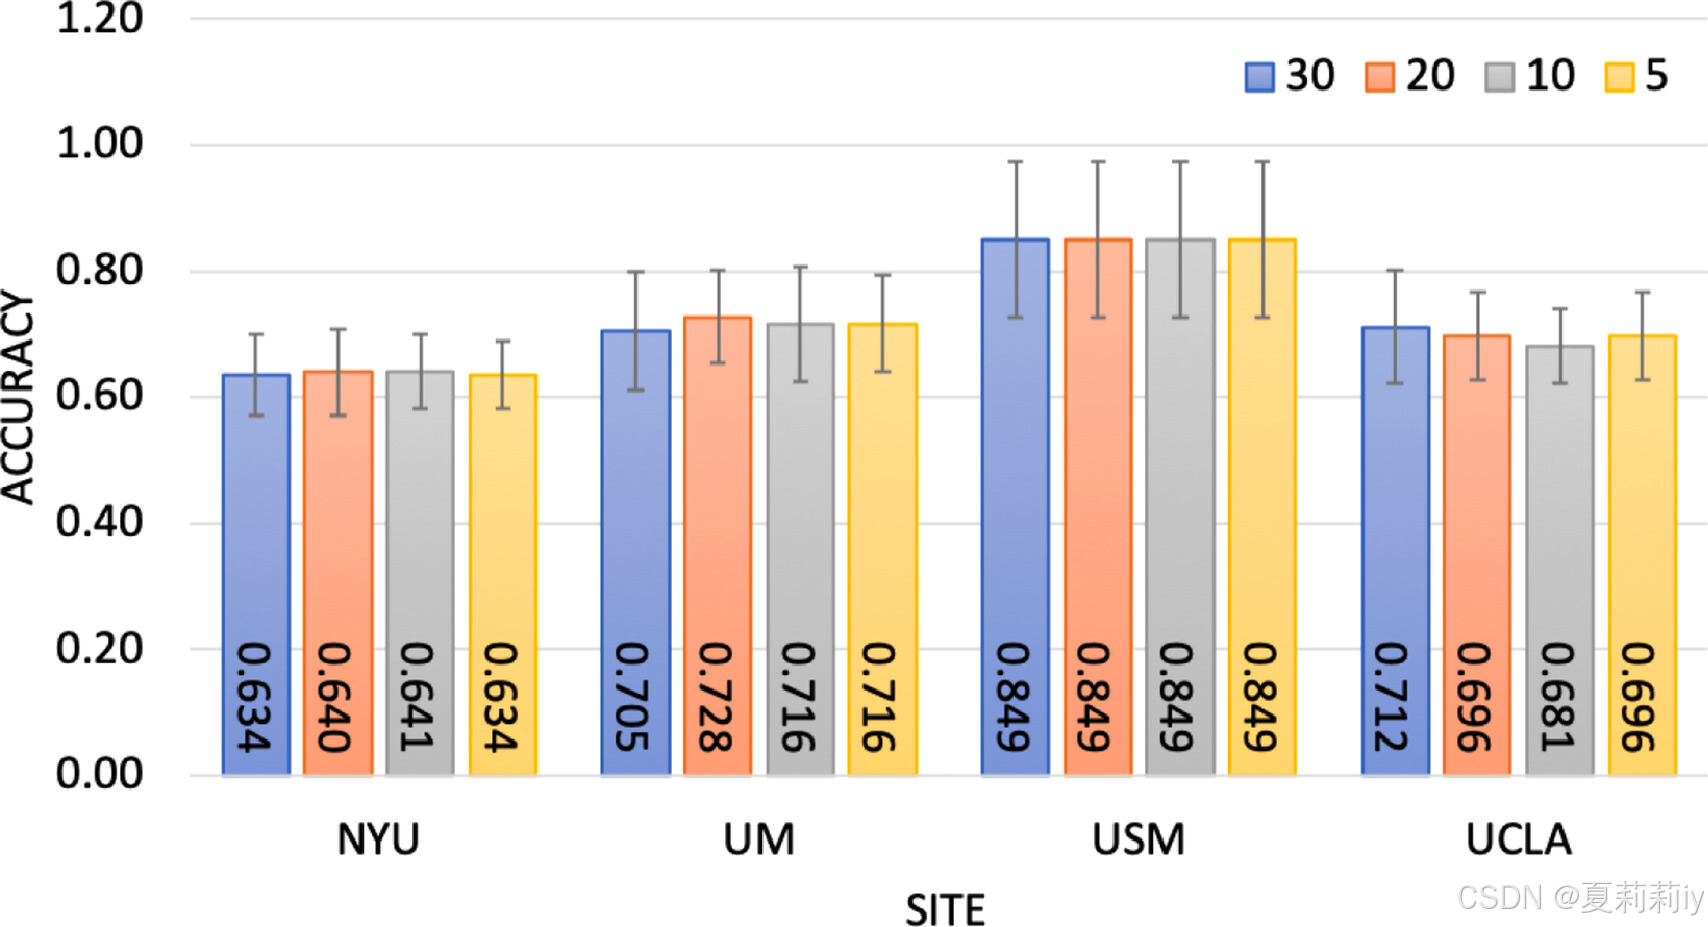

⑨ ablation:

no significant difference